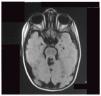

Comunicamos el caso de un varón de 2 años de edad, remitido con historia de hipotonía y retardo en el desarrollo psicomotor. Al examen físico en la consulta de genética se encuentra: pliegue epicántico bilateral, abombamiento frontal, occipucio prominente, labio superior triangular, paladar ojival, polidactilia postaxial en mano izquierda, además de hipotonía. Con estos hallazgos, se solicitó una RM de cerebro, la cual mostró el signo clásico “del molar” (fig. 1), por ausencia de vermis cerebeloso, con lo cual se hizo el diagnóstico clínico de síndrome de Joubert. En estudios complementarios, la valoración por oftalmología fue informada como normal y las pruebas de función hepática estaban elevadas.

El signo del molar se observa en los cortes axiales de neuroimágenes, como la tomografía computarizada y la RM de cerebro, y se caracteriza por una fosa interpeduncular posterior profunda, pedúnculos cerebelares superiores engrosados y elongados, además de hipoplasia o agenesia del vermis cerebeloso1.